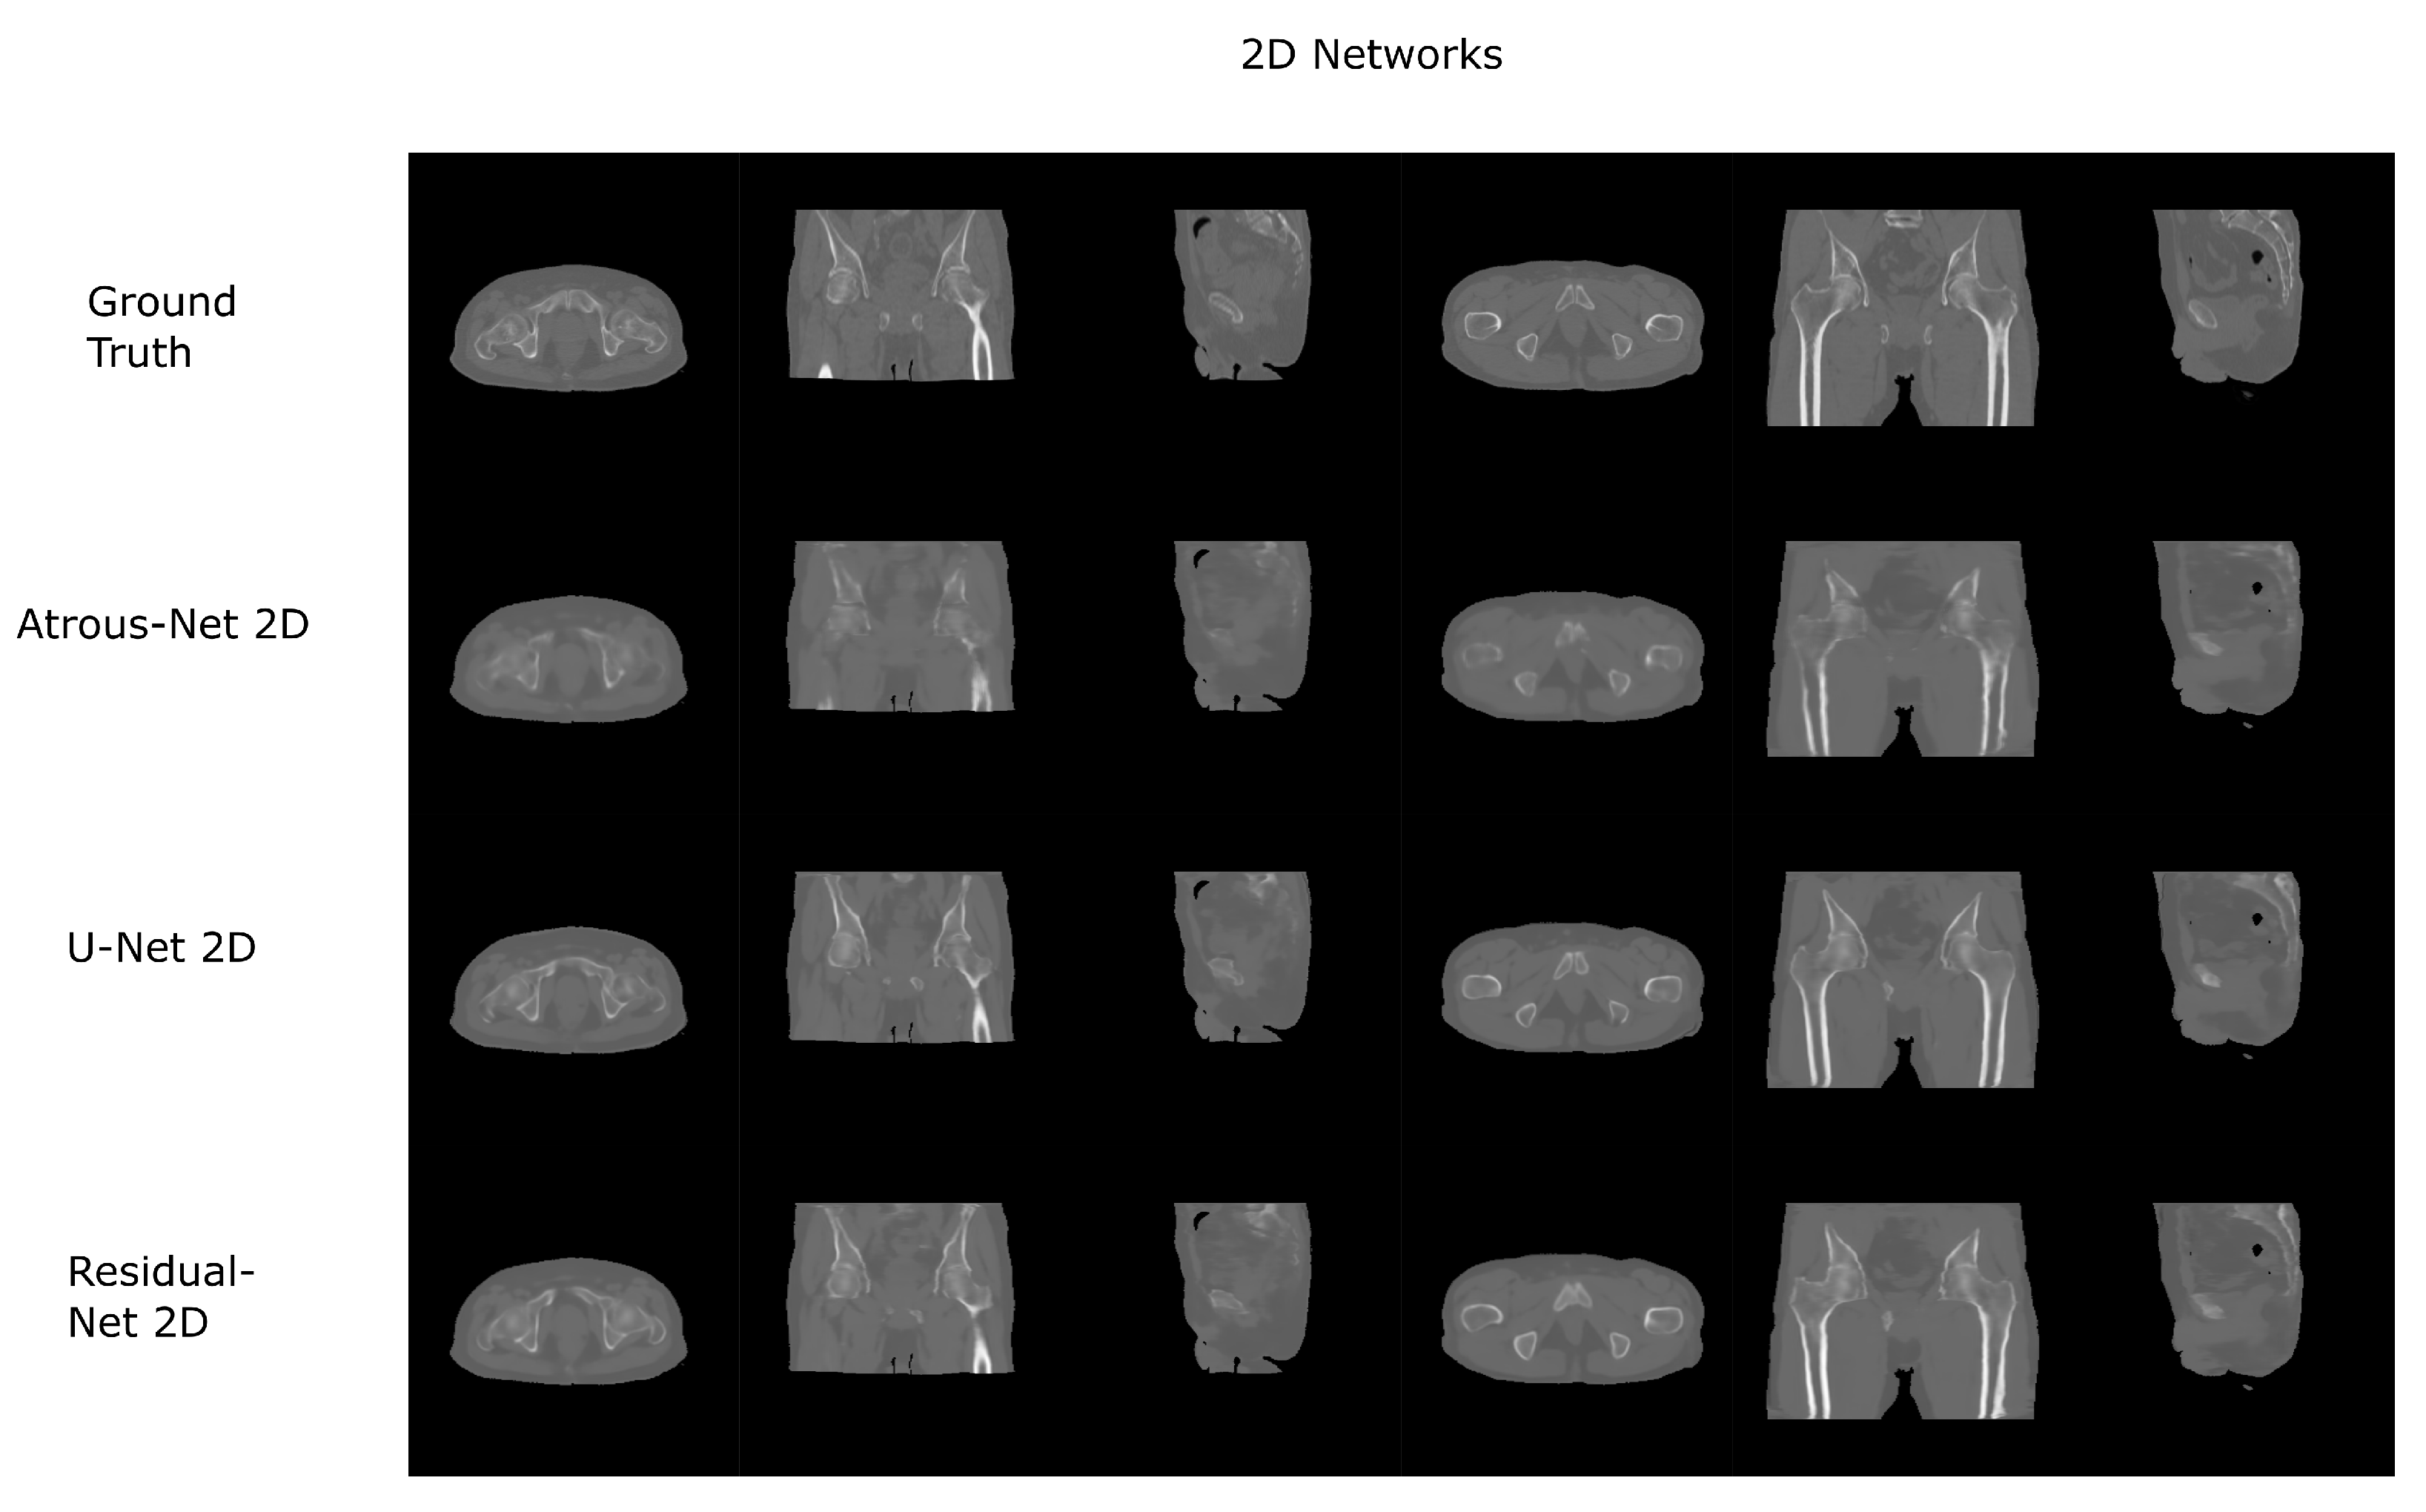

Figure 8.

Pelvis results using 2D networks.

The results for all tissues using the pelvis dataset are depicted in Table 16, Table 17 and Table 18; the results using only the bone voxels are detailed in Table 19, Table 20 and Table 21; the results using only the fat voxels are detailed in Table 22, Table 23 and Table 24; and the results using only the soft-tissue voxels are detailed in Table 25, Table 26 and Table 27. In the pelvis dataset all networks performed very similar when all tissues were considered. However, 3D networks obtained slightly worse results when assessing bone alone and very similar results for all tissues. The best network in the bone dataset was the 2D Residual network that obtained a MAE of 201.56 HU, a PSNR of 23.20 and a Pearson Coefficient of 0.476 in the bone. Additionally, the error in bone with all networks increased when the 3D scheme was used. The ANOVA test for the 2D results reported a statistically significant effect of the networks in all tissues and bone MAE (all tissues: , ; bone: , ) and PSNR (all tissues: , , bone: , ). According to 3D results, the ANOVA test did not expose statistically significant differences when using different architectures on all tissue MAE (all tissues: , ; bone: , ) and PSNR (all tissues: , ; bone: , ). Post hoc Student’s t-test is depicted in Table 28 and Table 29. It reveals that the Residual-net and Atrous-net did not provide statistically significant differences. Visual result examples of pelvis pseudo-CTs are depicted in Figure 8 and Figure 9. Table 30 shows the time needed to synthesize a whole pelvis volume using the different architectures.

In case the anatomy does not have complex structures across slices, 3D schemes are not the best option. Moreover, if the input image has very similar areas -as in pelvis acquisitions-, 3D patches will not satisfactory synthesize the pseudo-CT due to the lack of contextual information. In this scenario, according to our results, it would be better to use a 2D scheme. Specifically, the residual network obtained the best results in 2D (), which is consistent with the results in general computer vision, where 2D approaches are used [26,39].

In the pelvis dataset, the results were quite similar between networks, having differences in a range of 5% in the bone. This could be due to the input data used in the experiment: the Dixon-VIBE MRI. The Dixon-VIBE, as shown in Figure 2, does not depict the bone well. Moreover, it is fairly probable that the information to generate the pseudo-CT that it is contained in the image is low or moderate compared to T1 acquisitions (see Figure 1). That is, the networks gave similar results because the information that can be extracted from the input images is limited. However, Dixon-VIBE is the standard acquisition in PET attenuation correction and it is usually easier to have access to this type of acquisitions for the pelvis anatomy. Therefore, the type of network that is implemented does not have a great impact on the results.